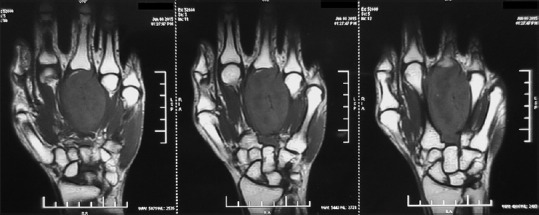

Four cycles of induction chemotherapy with vincristine, adriamycin, and cyclophosphamide (VAC) alternating with ifosfamide and etoposide (IE) regimen were administered as per the INT-0091 protocol.[4] A repeat MRI of the left hand showed an increase in the size of tumor to 7.3 cm × 3.8 cm × 3.7 cm. The tumor was involving the third metacarpal bone with extension into proximal and distal epiphysis. There was involvement of the third metacarpophalangeal joint, base of the second metacarpal bone, and the interosseous muscles [Figure 2].

| Figure 2:Repeat magnetic resonance imaging of the left hand after induction chemotherapy showing a 7.3 cm × 3.8 cm × 3.7 cm tumor involving the third metacarpal bone with extension into proximal and distal epiphysis, third metacarpophalangeal joint, base of the second metacarpal bone, and the interosseous muscles